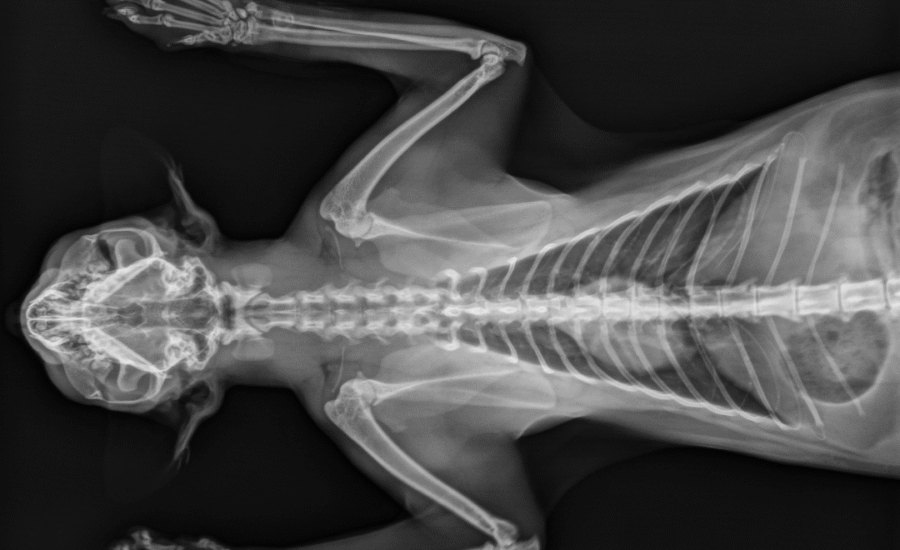

De diergeneeskunde staat aan de vooravond van een digitale revolutie. Slimme diagnostiek bij dieren: van röntgen tot MRI is volop in ontwikkeling dankzij AI-technologie. Waar dierenartsen nu nog vooral vertrouwen op hun getrainde oog, kan kunstmatige intelligentie